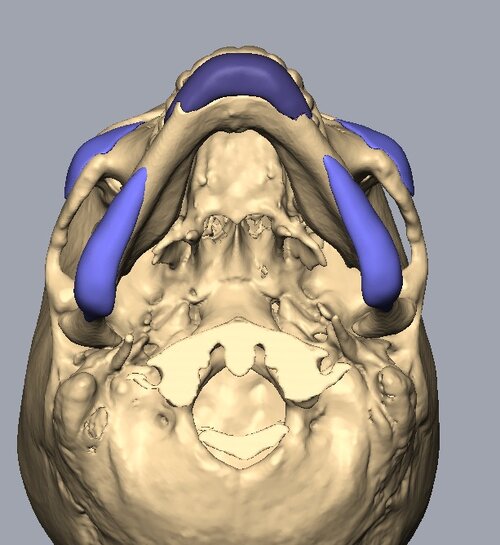

Recieved the draft 1 of the design, what changes should i ask for?? a couple of things i can think of are malar implants not giving enough lateral protrusion, gonion flaring.

I also am planning to include infra implants as well.